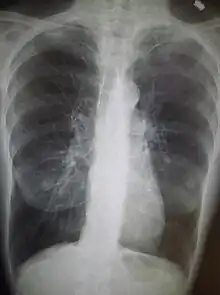

Examens complémentaires

- Radiographie pulmonaire pour les épisodes aigus ;